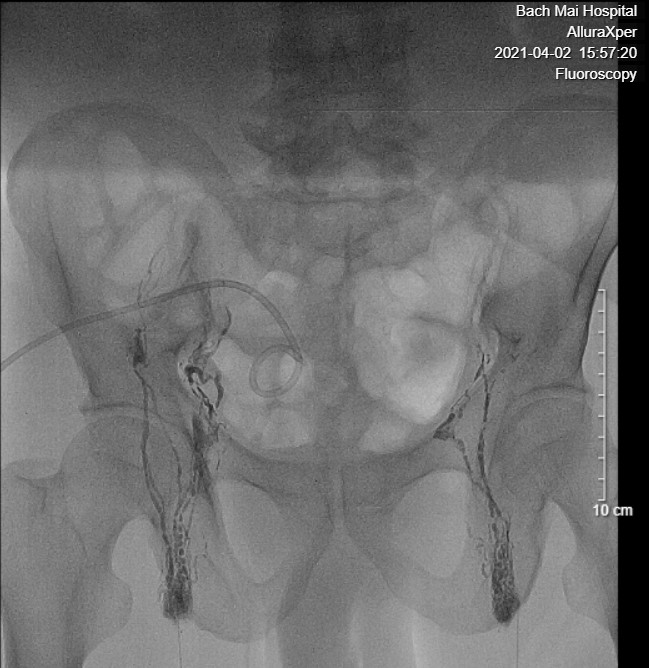

| Ảnh 1: Lipiodol được tiêm vào hạch bẹn hai bên, vào bạch mạch tiểu khung và di chuyển dần lên trên. | Ảnh 2: Lipiodol đi vào bạch mạch sau phúc mạc, sau đó đi vào bể dưỡng chấp, vào ống ngực, rồi đổ vào tĩnh mạch dưới đòn trái |